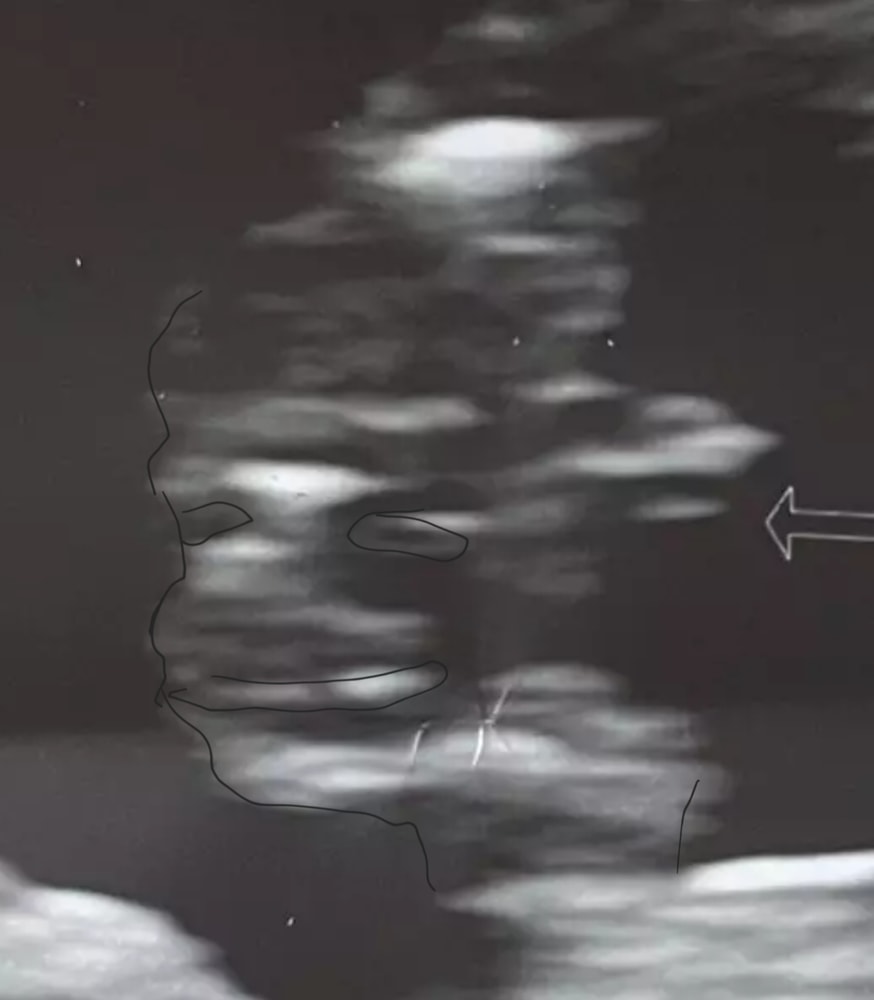

Честно говоря, я тут вообще ничего не понимаю. Это скрин с видео? Или врач вам вывел это "что-то" на экран для снимка?

В теории, если это срез внизу, тогда можно предположить, что это мальчик. Но я не понимаю, на самом деле, что это.

Дарина Савенкова, обвела красным. сверху, снизу ножки, посередине писюнчик. вид снизу со стороны попы, на мальчика больше похоже